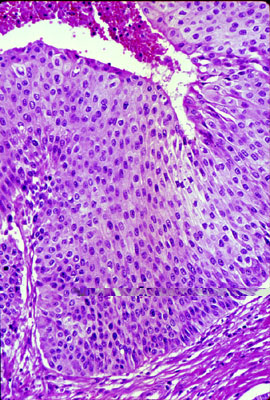

Click picture to enlarge. Close window to return